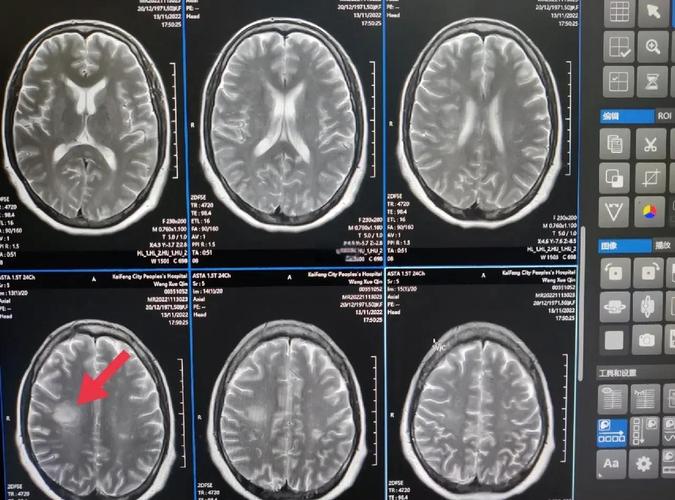

(图片来源网络,侵删)

- 头颅MRI+DWI+MRA/CTA: MRI是发现脑梗病灶最敏感的检查,MRA(磁共振血管成像)或CTA(CT血管成像)可以查看脑血管有无狭窄或闭塞。

- 颈动脉超声: 检查颈部大动脉有无斑块和狭窄。